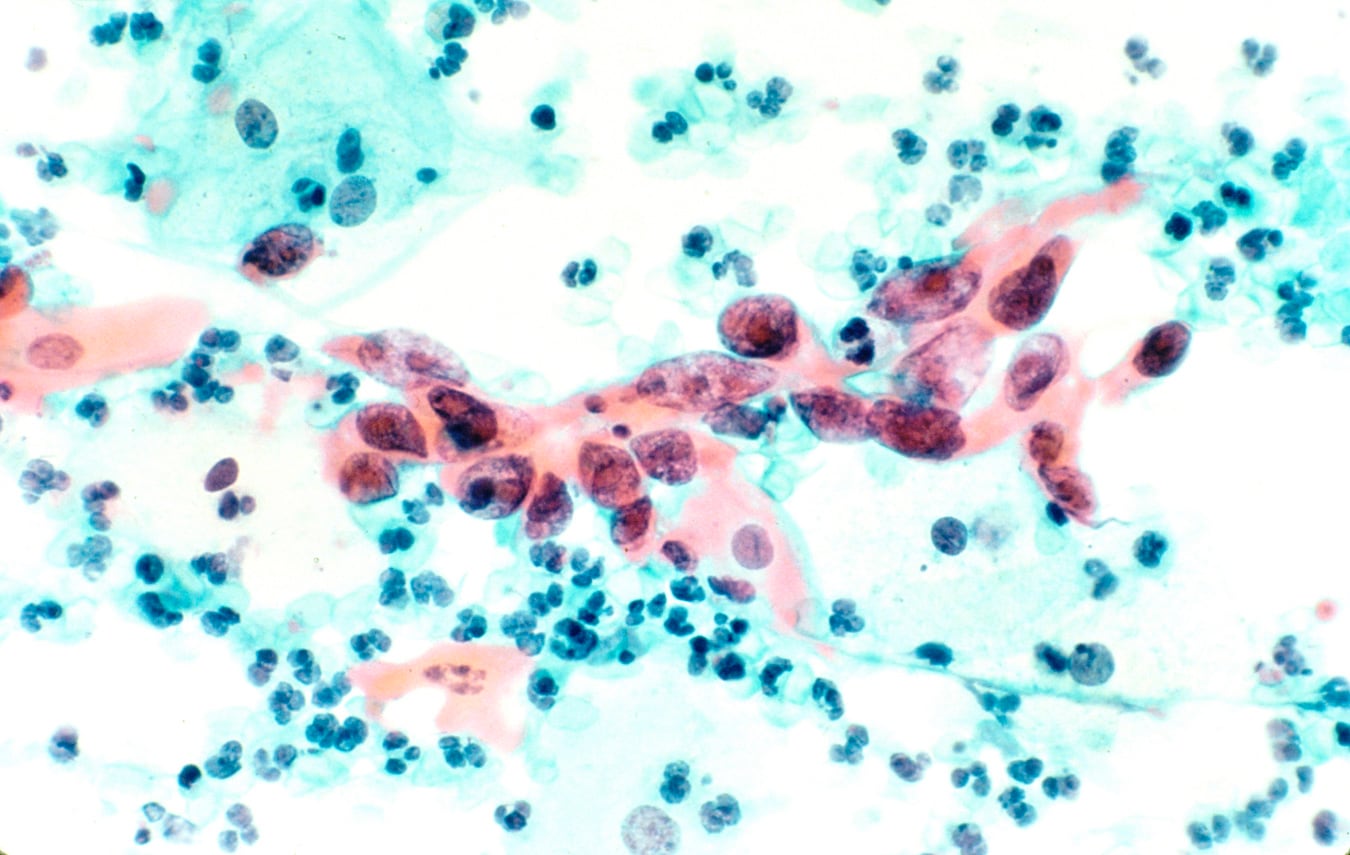

Las consecuencias sanitarias de la baja cobertura se reflejan en las estadísticas. El cáncer de cuello uterino, provocado en el 99% de los casos por el VPH, figura entre las principales causas de mortalidad por cáncer en mujeres jóvenes. De acuerdo con la OMS, cada año se diagnostican más de 600.000 nuevos casos a nivel global y fallecen más de 340.000 mujeres por esa enfermedad.

En Argentina, el Observatorio Global del Cáncer reportó 4.600 nuevos diagnósticos y más de 2.200 muertes anuales. El virus también provoca cánceres de ano, vagina, vulva y orofaringe, afectando tanto a mujeres como a varones.

Entre los hombres, la incidencia de tumores orofaríngeos vinculados al VPH ya supera en algunos países los casos de cáncer de cuello uterino en mujeres.